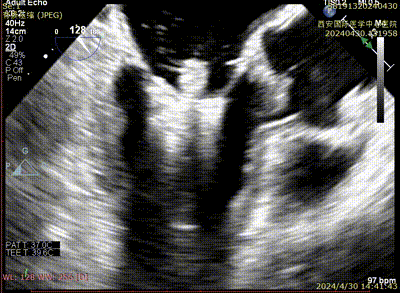

Case 1影像资料

房间隔穿刺

二尖瓣夹系统植入

二尖瓣夹瓣上Trajectory

二尖瓣夹进入左室

二尖瓣夹捕获瓣叶

二尖瓣夹夹闭

术后二尖瓣反流评估

术后结果